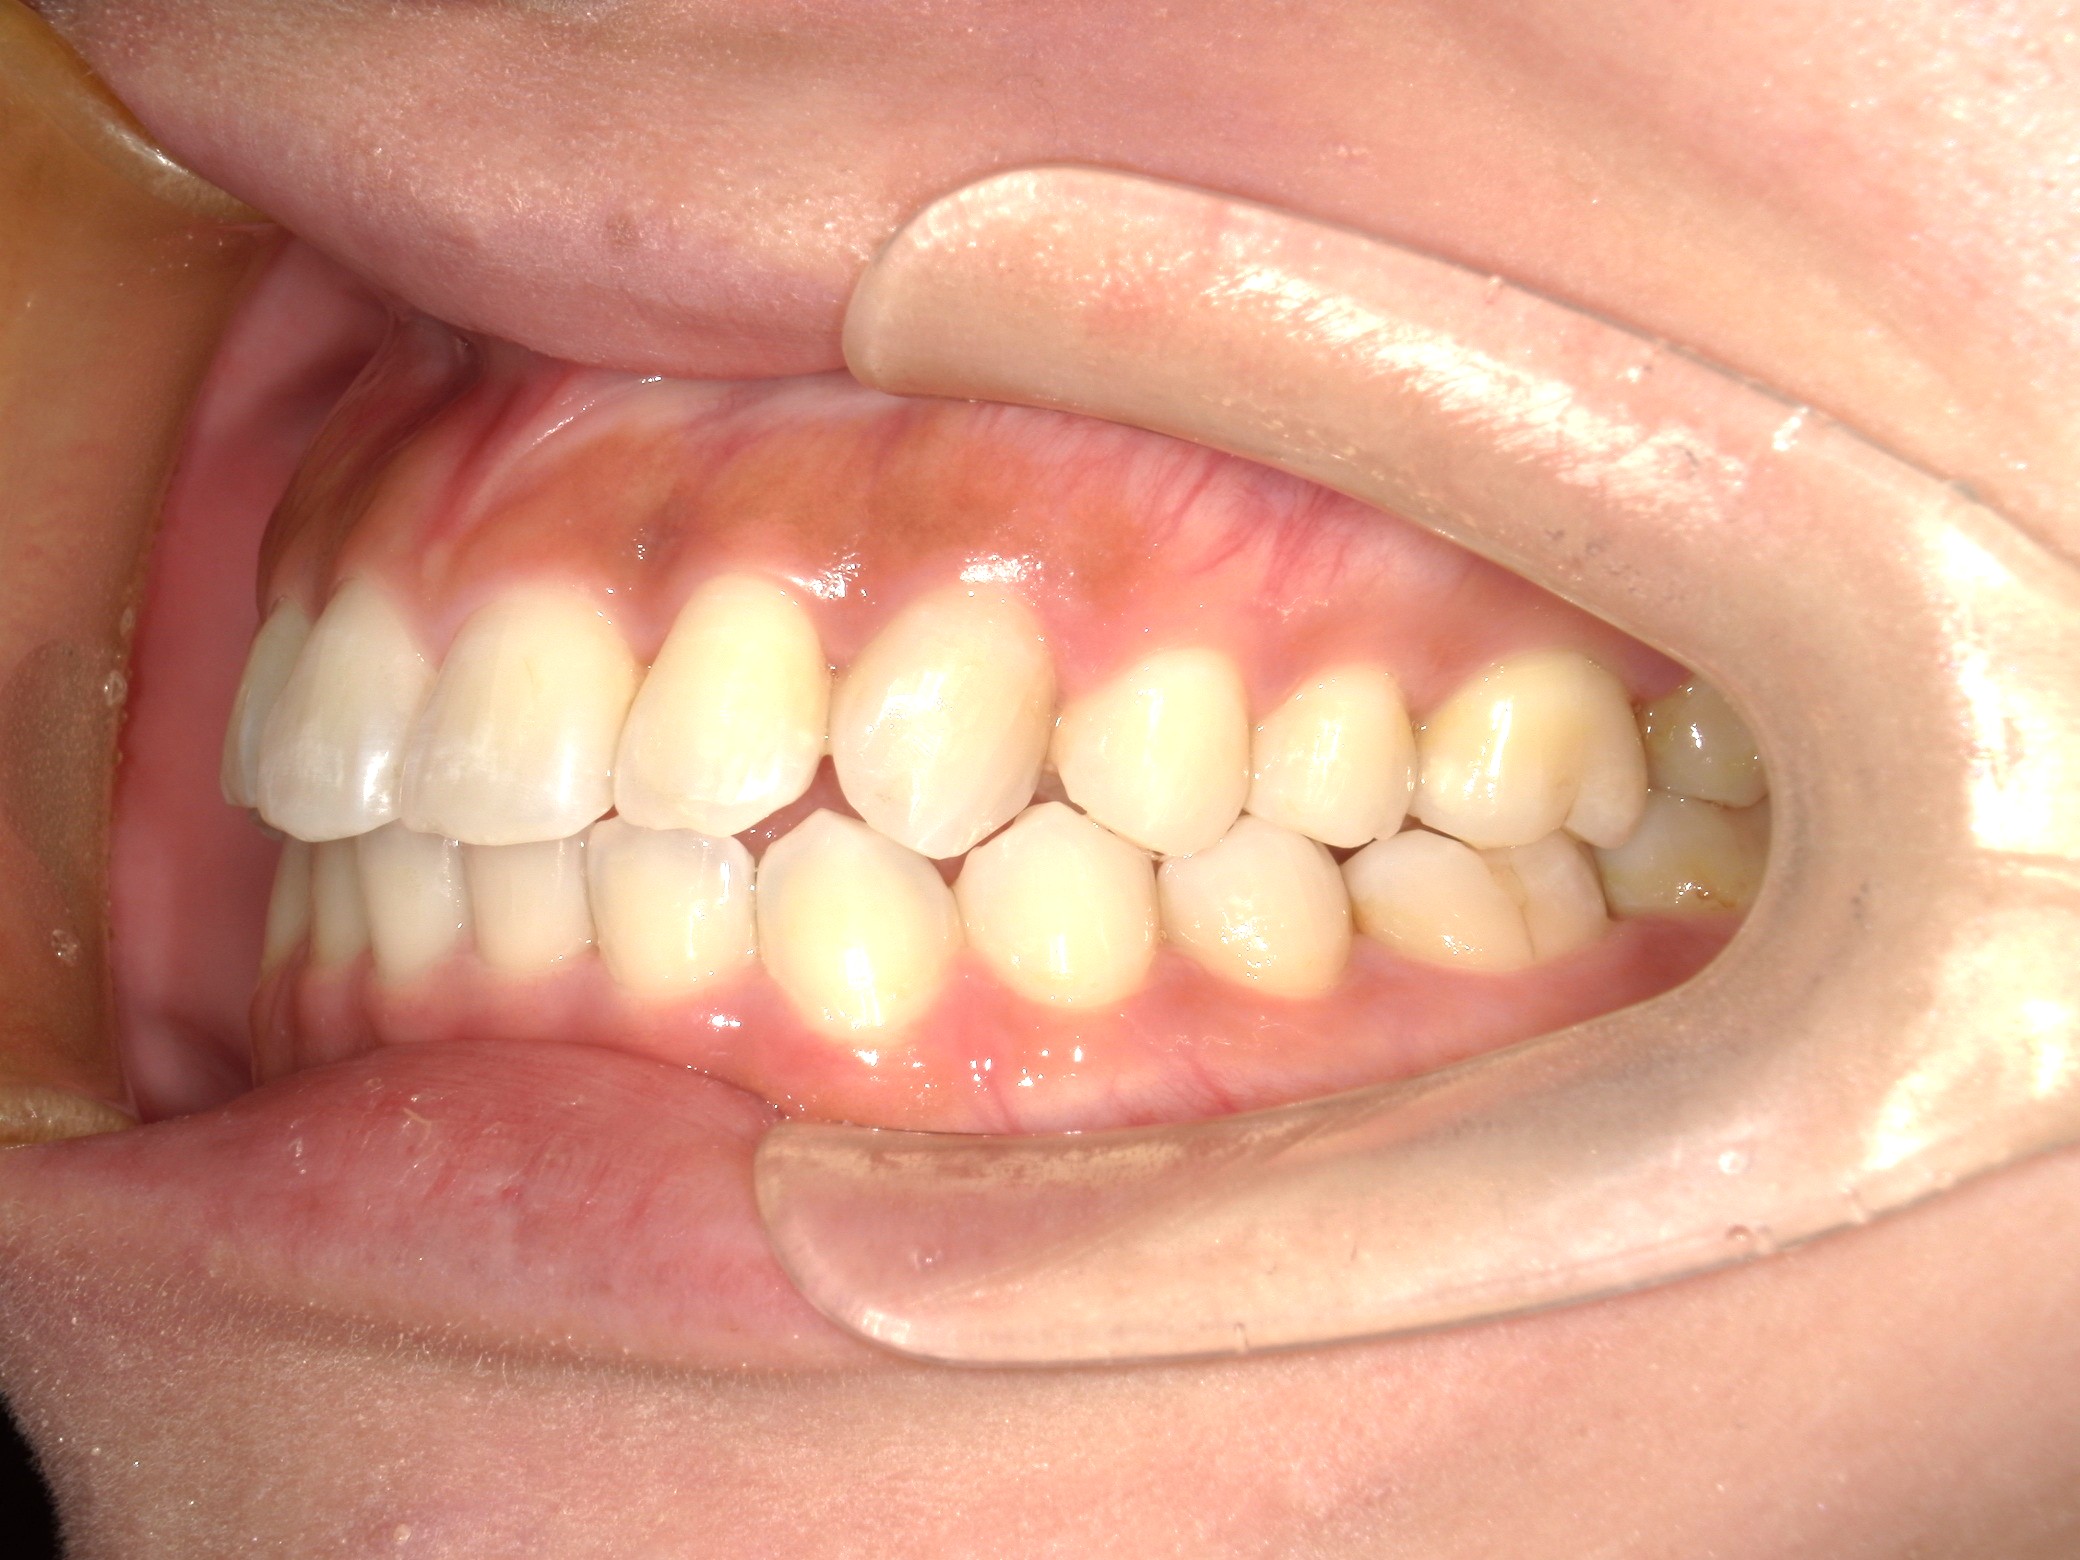

口内右

治療前

治療後